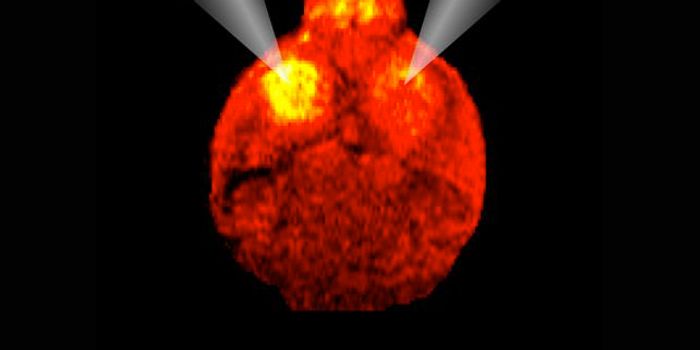

OCT 19, 2017CancerTo fuel their growth and edge out healthy cells, breast cancer cells recycle a waste product into nutrients, researchers ...